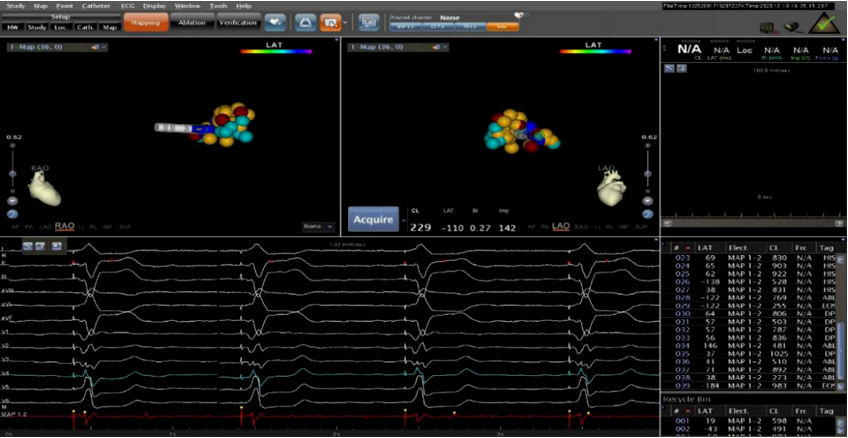

▲房室结改良成功

为减少患者的住院率,李润琴主任团队考虑到患者房颤时间长、药物治疗控制心室率效果欠佳,且心脏重构明显、房颤的射频消融术成功率低、复发率高等情况,立刻制定出“房室结改良+ICD起搏、房室结改良+左束支起搏”等几套手术方案。在主治医生与患者家属充分沟通病情后,结合患者及家属的经济状况,最终决定行房室结改良+左束支起搏植入术,最大限度地保持心脏电和机械的同步性,从而达到“双赢”——控制心室率及改善心衰发生。手术过程顺利,李润琴主任团队通过准确的定位,娴熟的手法,还给患者一颗“强心脏”。